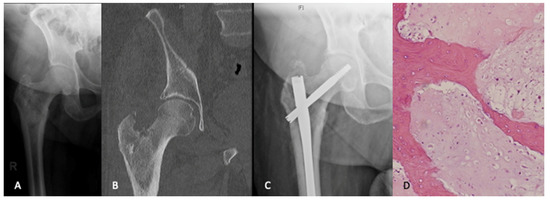

Osteosynthesis

- Cappellari, A.; Trovarelli, G.; Crimì, A.; Pala, E.; Angelini, A.; Berizzi, A.; Ruggieri, P. New concepts in the surgical treatment of actual and impending pathological fractures in metastatic disease. Injury 2020. [Google Scholar] [CrossRef]